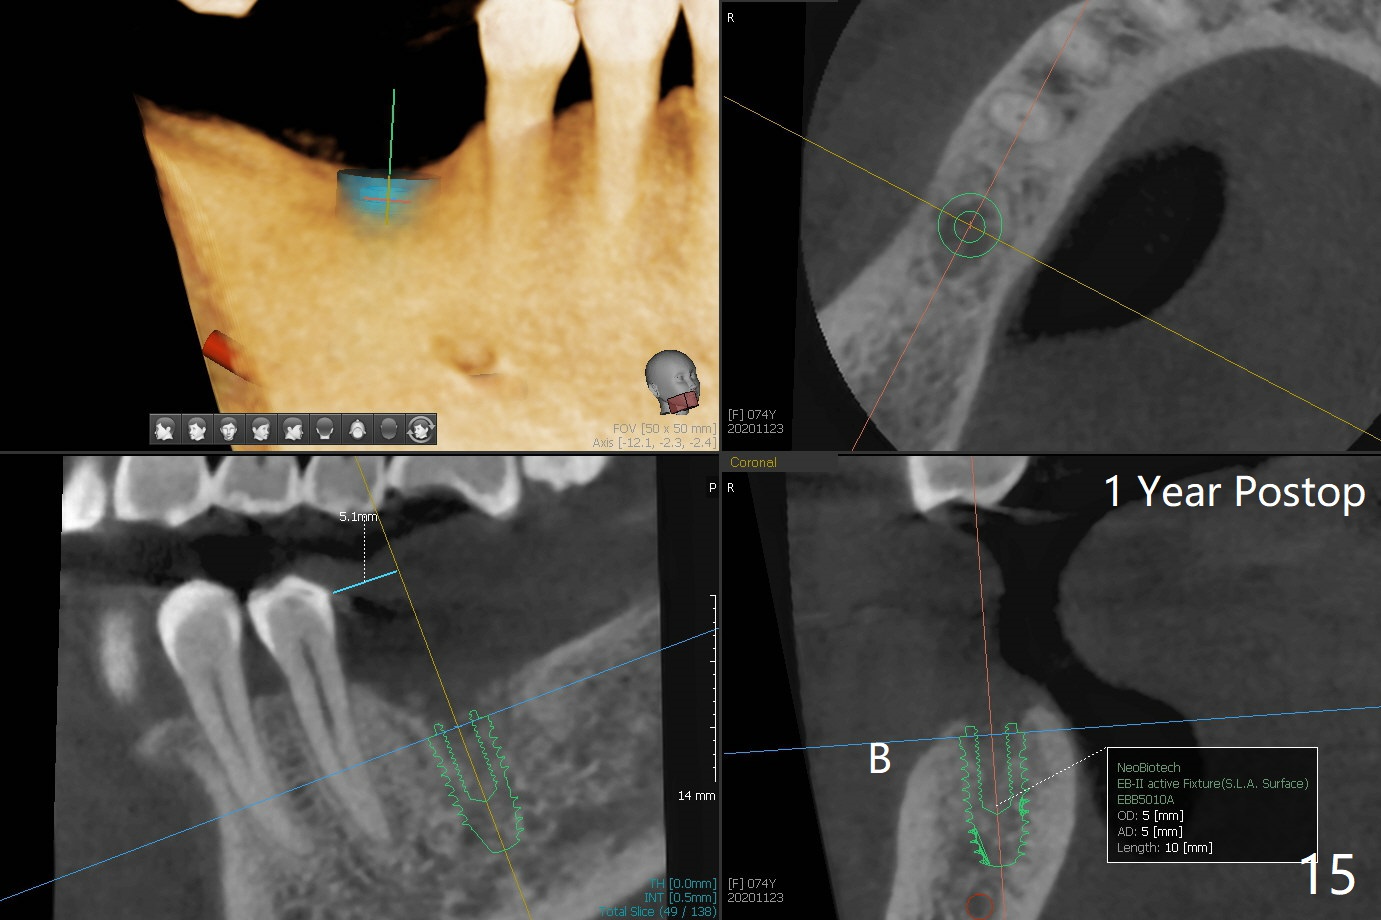

There are signs of periimplantitis at #30 eleven months postop (Fig.1 (* bone loss)). The bony defect (Fig.2) will be filled with allograft mixed PRF liquid to form sticky bone (Fig.3,4), followed by PRF membrane (not shown) and a piece of 6-month membrane (Fig.5). A hole is cut so that the 6-month membrane can slide down the abutment (Fig.2,5 A) to cover the bone graft around the implant (Fig.2,7 I). Setting acrylic is applied around the abutment and neighboring teeth for further protection and holding (Fig.8). The periimplantitis does not resolve nearly 7 months post graft. The implant will be removed. Prepare UF extra wide kit and try to insert 6.5 or 7.0 mm tap. Also prepare sticky bone and Cytoplast for wound closure. Implant removal involves surgical handpiece, 6.2/7 mm trephine bur, elevators, and implant driver. The defect is large (Fig.9) with the low buccal crest (Fig.10) and bone graft with PRF ("sticky bone") is placed, covered by PRF and 6-months membrane (Fig.11). The next implant will be placed with guide. If oral hygiene is not ideal, choose a bone level implant. The middle of the wound dehiscences slightly 8 days postop (Fig.12), accounting for mild loss of bone graft 1 year postop (Fig.14). The keratinized gingiva is apparently wide 1 year postop (Fig.13). There is mild loss of bone graft in the middle of the superficial area (Fig.14). The buccal plate seems to regenerate 1 year postop (pandemic delay, Fig.15).